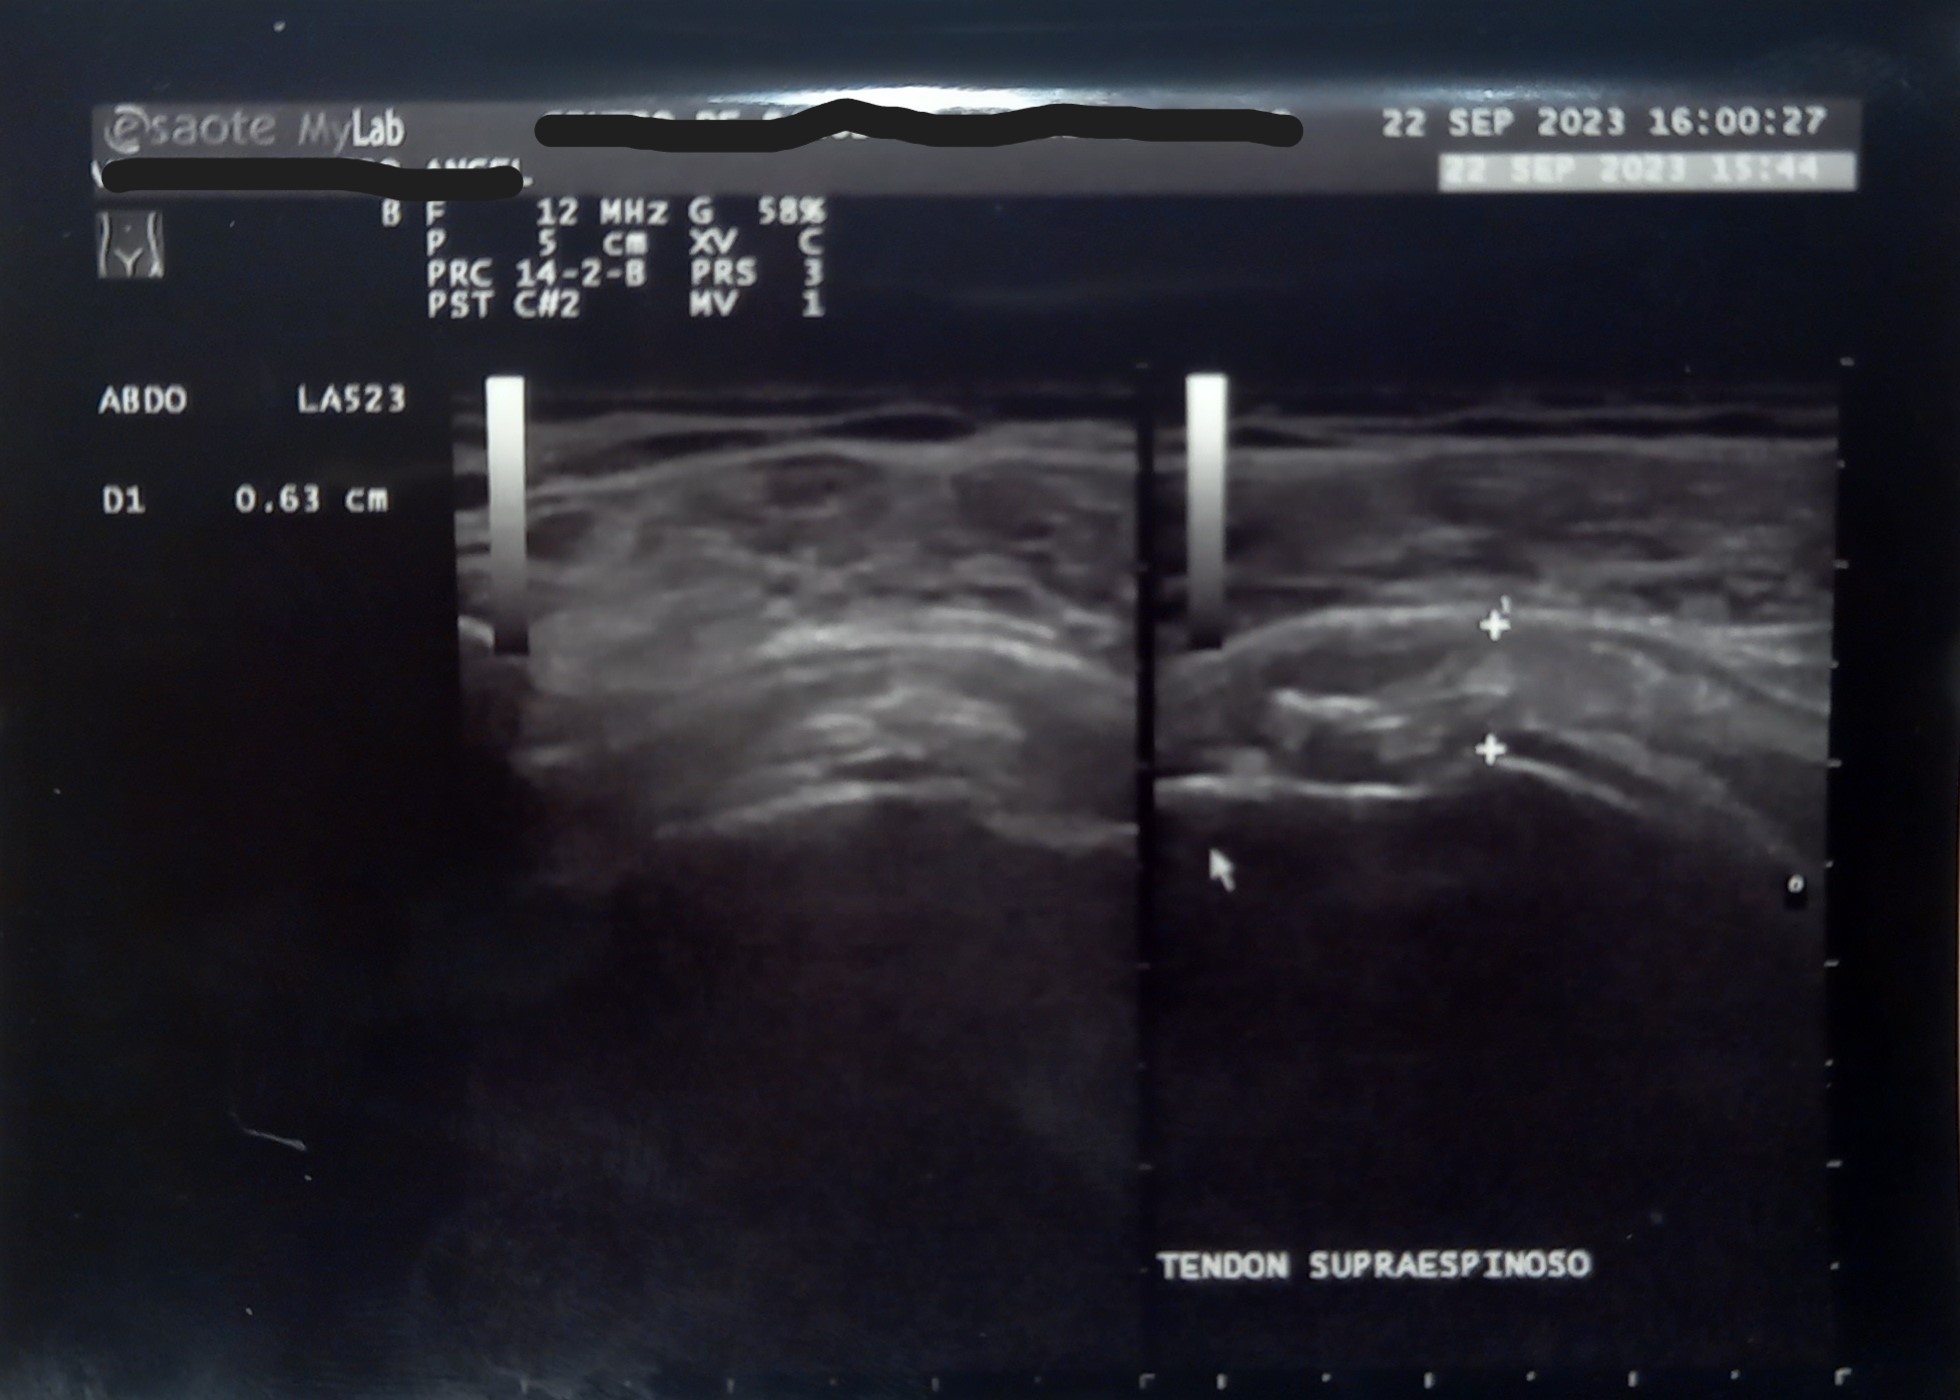

Hallazgos ecográficos

Ecografía en consulta de Atención Primaria. Se observa en la ecografía de partes blandas Patrón heterogéneo en región de tendón supraespinoso, con áreas hipo ecoicas y banda hiperecogenica compatible con tendinitis calcificante del tendón del supraespinoso. Tendón sub-escapular con áreas hipoecoicas en su trayecto que puede atribuirse a tendinosis de larga evolución.